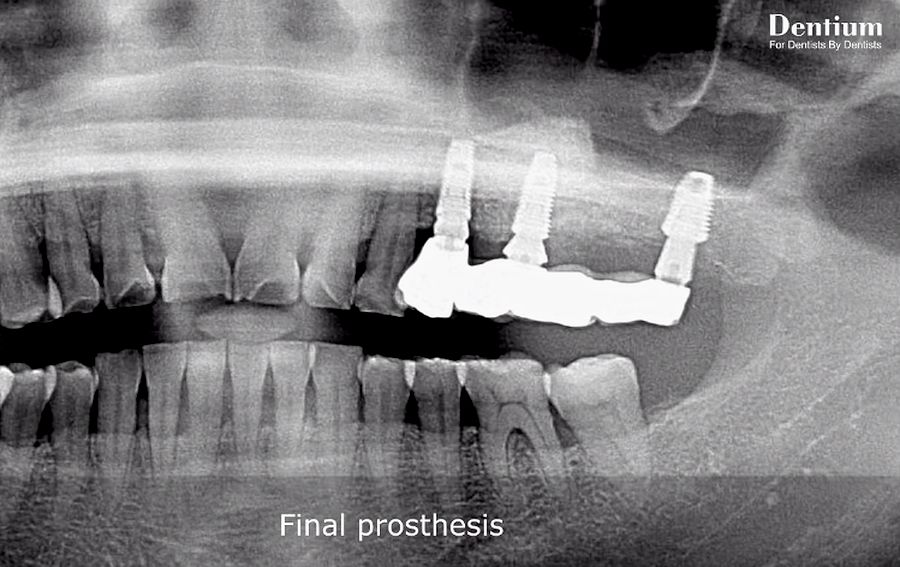

Total Solution for Sinus (Lateral approach) YouTube What Is A Sinus Elevation Web a sinus lift (also called a maxillary sinus augmentation or sinus floor elevation) is a surgical procedure done to prepare for dental implants. Web a sinus augmentation is performed when a patient has insufficient bone in their upper jaw to support a dental implant. In the posterior maxillary region, the vertical bone height is often insufficient to receive an. What Is A Sinus Elevation.